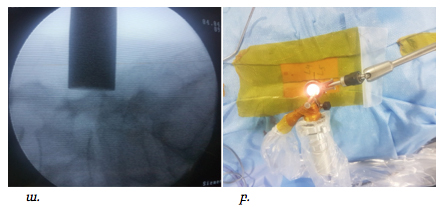

Վիրահատությունները կատարվել են ընդհանուր անզգայացման պայմաններում: Հիվանդի դիրքը փորի վրա էր: Նախքան վիրահատությունը կատարվում էր անհրաժեշտ միջողային աճառի մակարդակի որոշում՝ համաձայն կողմնային պրոեկցիայում կատարված ռենտգեն հետազոտության: Մաշկի գծային կտրվածքըկատարվում էր միջին գծից լատերալ մոտ 1.5-2սմ այնպես, որ համապատասխաներ ելունային հոդի մեդիալ սահմանին, ինչը որոշվում է հսկիչ ռենտգեն հետազոտմամբ առաջահետին պրոեկցիայում:

Վիրահատական մուտքի պլանավորումը ցույց է տրված նկար 1 և 2-ում:

Նկ. 1 Ներվիրահատական լուսանկար: Պատկերված է L4-L5 միջողային մակարդակի վիրահատման համար գծային կտրվածքը՝ մոտ 1.5սմ երկարությամբ (ցույց է տրված սլաքով)

Նկ. 2 Ներվիրահատական ռենտգեն նկար՝ վիրահատական մուտքի պլանավորում

ա. Կողմնային պրոեկցիայում ասեղը տեղադրված է L4-L5 մակարդակին:

բ. Առաջահետին պրոեկցիա՝ ասեղի ծայրը գտնվում է ելունային հոդի միջային եզրին